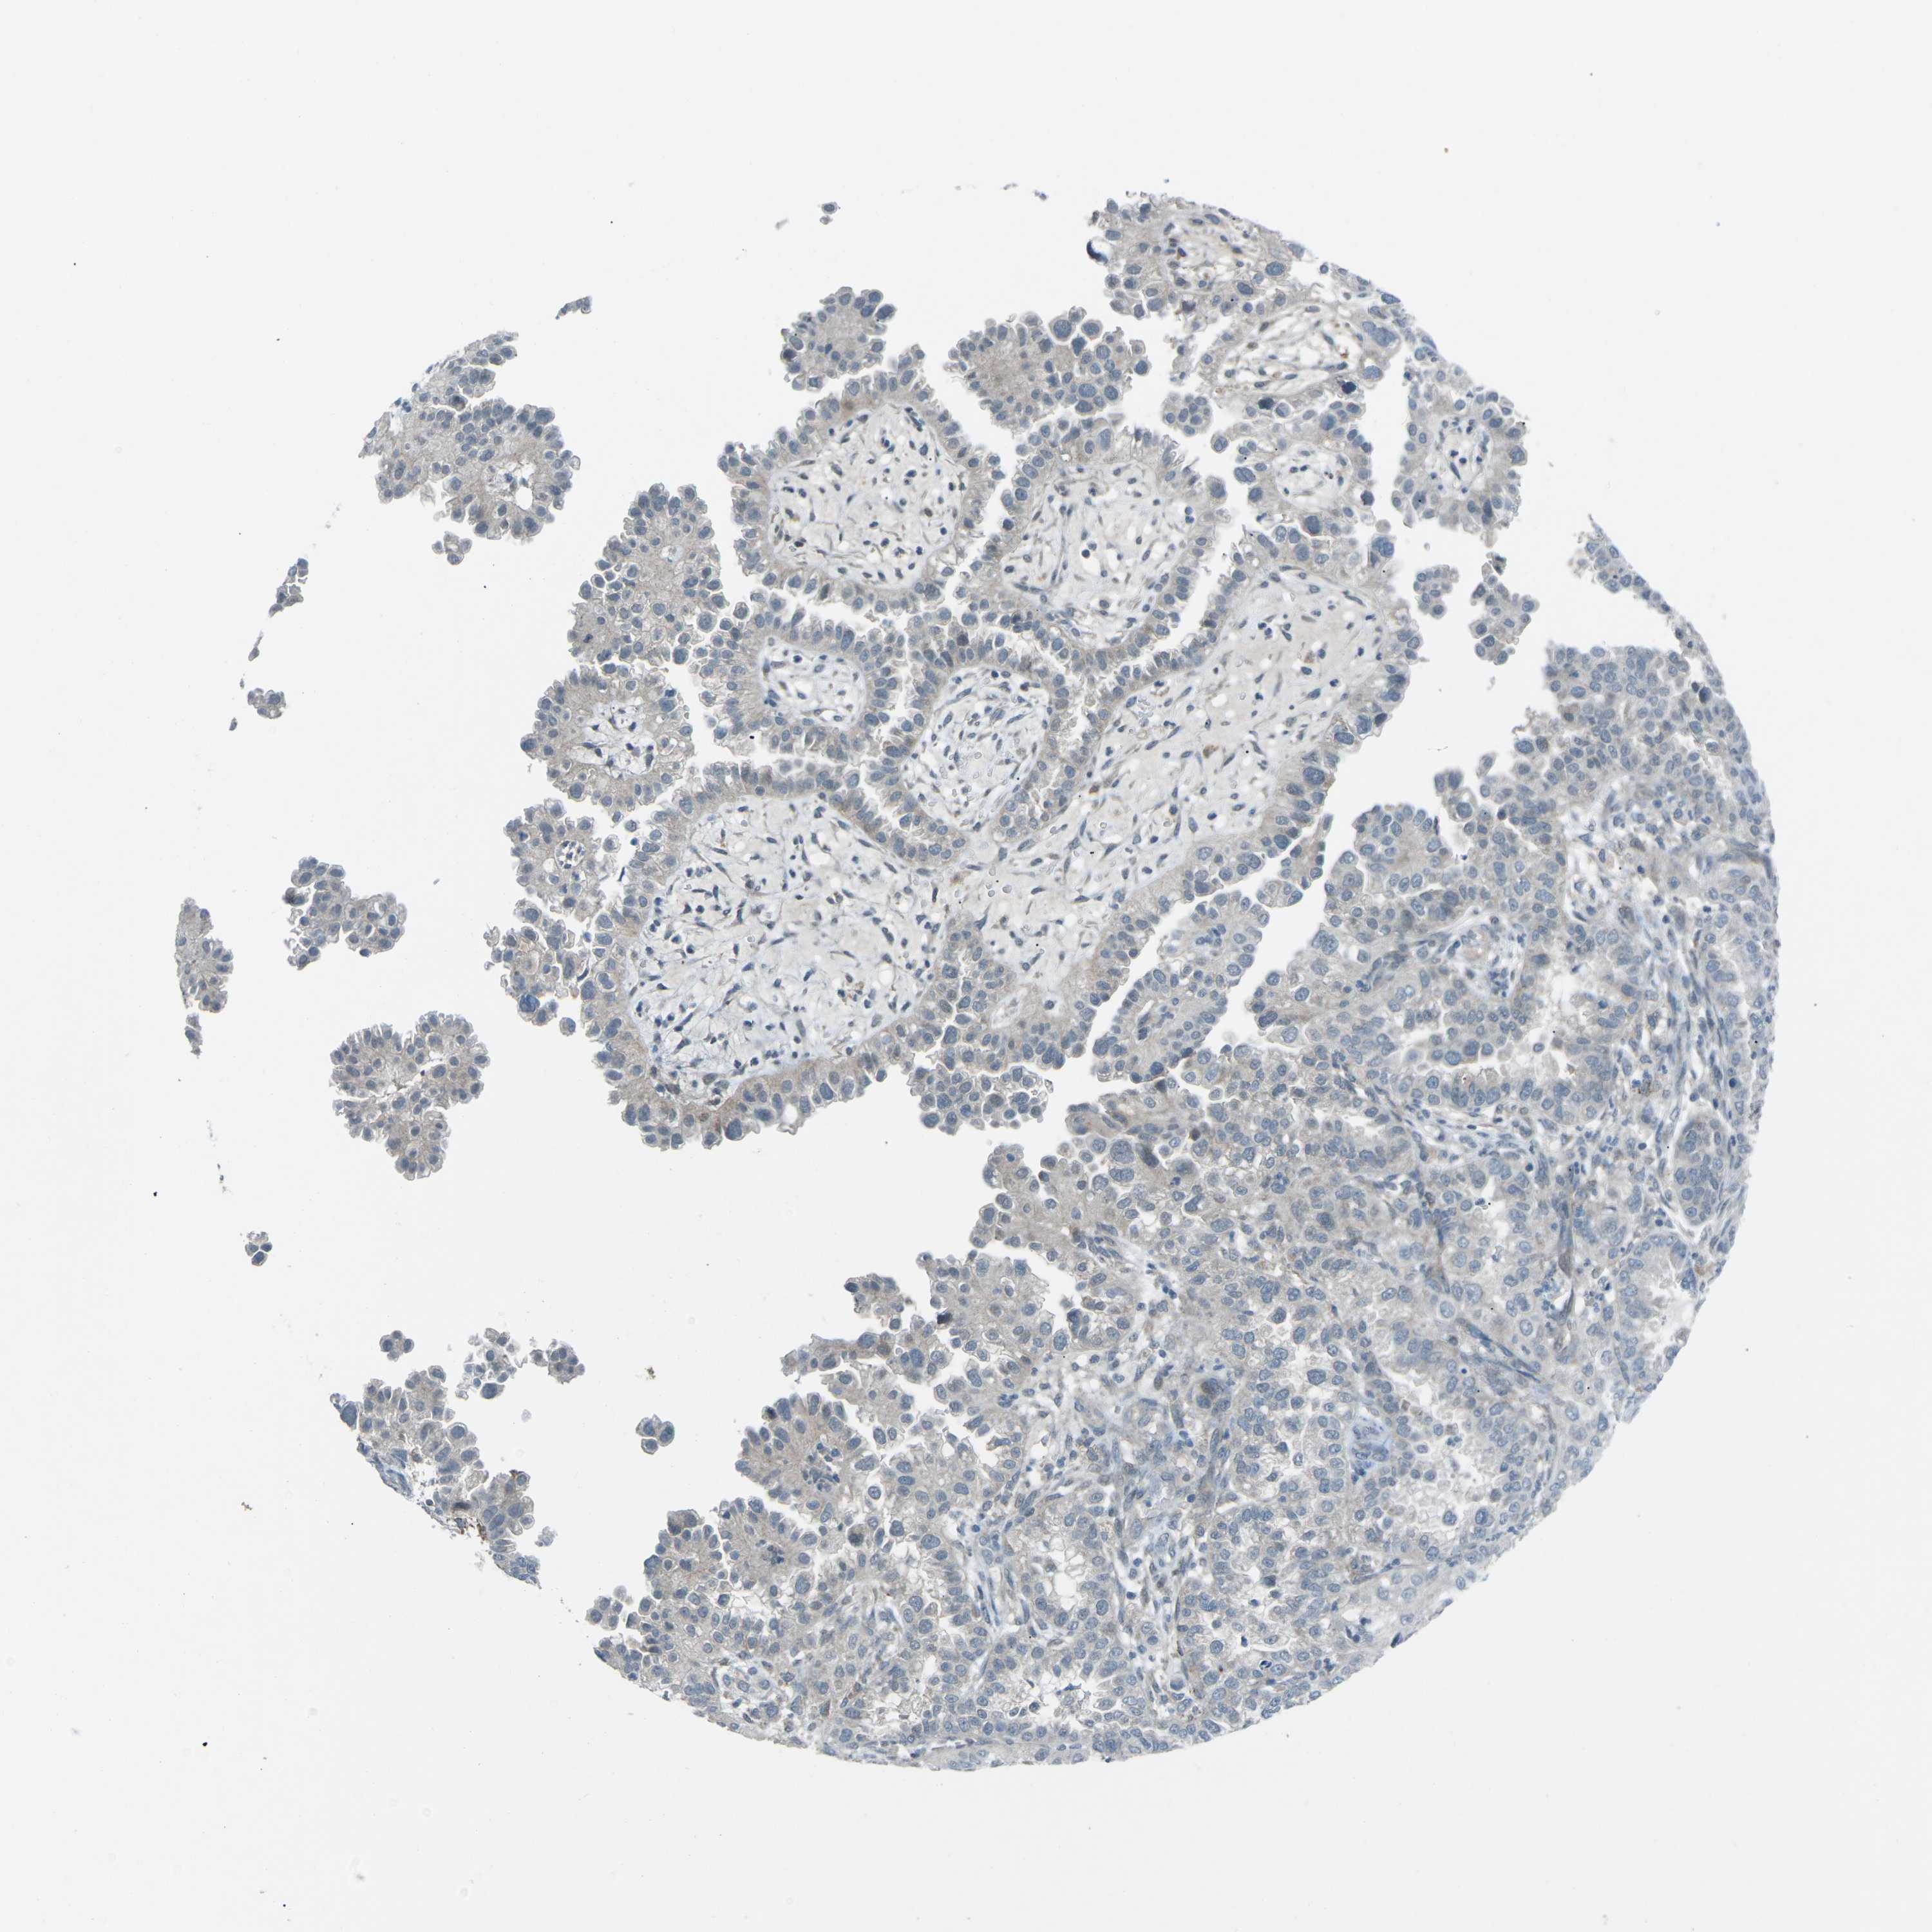

ENDOMETRIAL CANCER - Protein expressioni

A mouse-over function shows sample information and annotation data. Click on an image to view it in a full screen mode. Samples can be filtered based on level of antibody staining by selecting one or several of the following categories: high, medium, low and not detected. The assay and annotation is described here.

Note that samples used for immunohistochemistry by the Human Protein Atlas do not correspond to samples in the TCGA dataset.

Antibody stainingi

Antibody staining in the annotated cell types in the current human tissue is reported as not detected, low, medium, or high, based on conventional immunohistochemistry profiling in selected tissues. This score is based on the combination of the staining intensity and fraction of stained cells.

Each image is clickable and will lead to virtual microscopy that enables deeper exploration of all samples and also displays staining intensity scores, fraction scores and subcellular localization as well as patient and tissue information for each sample.

Antibody HPA006563

Antibody HPA006564

Antibody CAB003844

Antibody CAB016290

Staining

High

Medium

Low

Not detected

Intensity

Strong

Moderate

Weak

Negative

Quantity

>75%

75%-25%

<25%

None

Location

Nuclear

Cytoplasmic/membranous

Cytoplasmic/membranous,nuclear